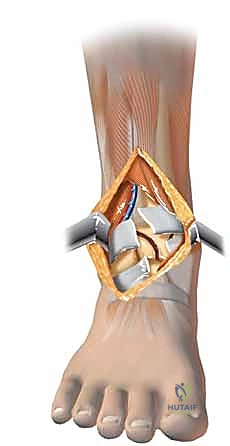

الخطوات الجراحية التفصيلية: إبداع التثبيت الداخلي المفتوح (ORIF)

في صنعاء، يطبق الأستاذ الدكتور محمد هطيف المبادئ الأربعة الكلاسيكية التي وضعها (Ruëdi and Allgöwer) والتي تم تحديثها بالتقنيات الحديثة، وتتمثل أهدافها في:

1. إعادة بناء مفصلية دقيقة (Anatomic Articular Reduction): لا مجال للخطأ هنا. يجب إعادة بناء السطح المفصلي بدقة المليمتر لتجنب احتكاك الغضاريف وحدوث خشونة مبكرة.

2. استعادة طول الطرف ومحاذاته (Restoration of Length and Alignment): لمنع العرج وتوزيع الوزن بشكل غير متساوٍ على الركبة والورك.

3. التطعيم العظمي (Bone Grafting): لملء الفراغات الناتجة عن انضغاط العظم الإسفنجي.

4. تثبيت الكسر المستقر (Stable Fixation): باستخدام شرائح ومسامير متطورة للسماح بالحركة المبكرة للمفصل.

في حوالي 90% من حالات كسور البيلون عالية الطاقة، نجد كسرًا مصاحبًا في عظم الشظية. هذا ليس مجرد تفصيل جانبي؛ بل هو مؤشر حاسم على مقدار الطاقة المدمرة التي امتصها الطرف، ويلعب دورًا محوريًا في استراتيجية الأستاذ الدكتور محمد هطيف الجراحية، حيث غالبًا ما يتم تثبيت الشظية أولاً كخطوة أساسية لاستعادة الطول التشريحي للطرف وضبط الدوران الصحيح قبل الانتقال للتعامل مع المفصل المفتت.